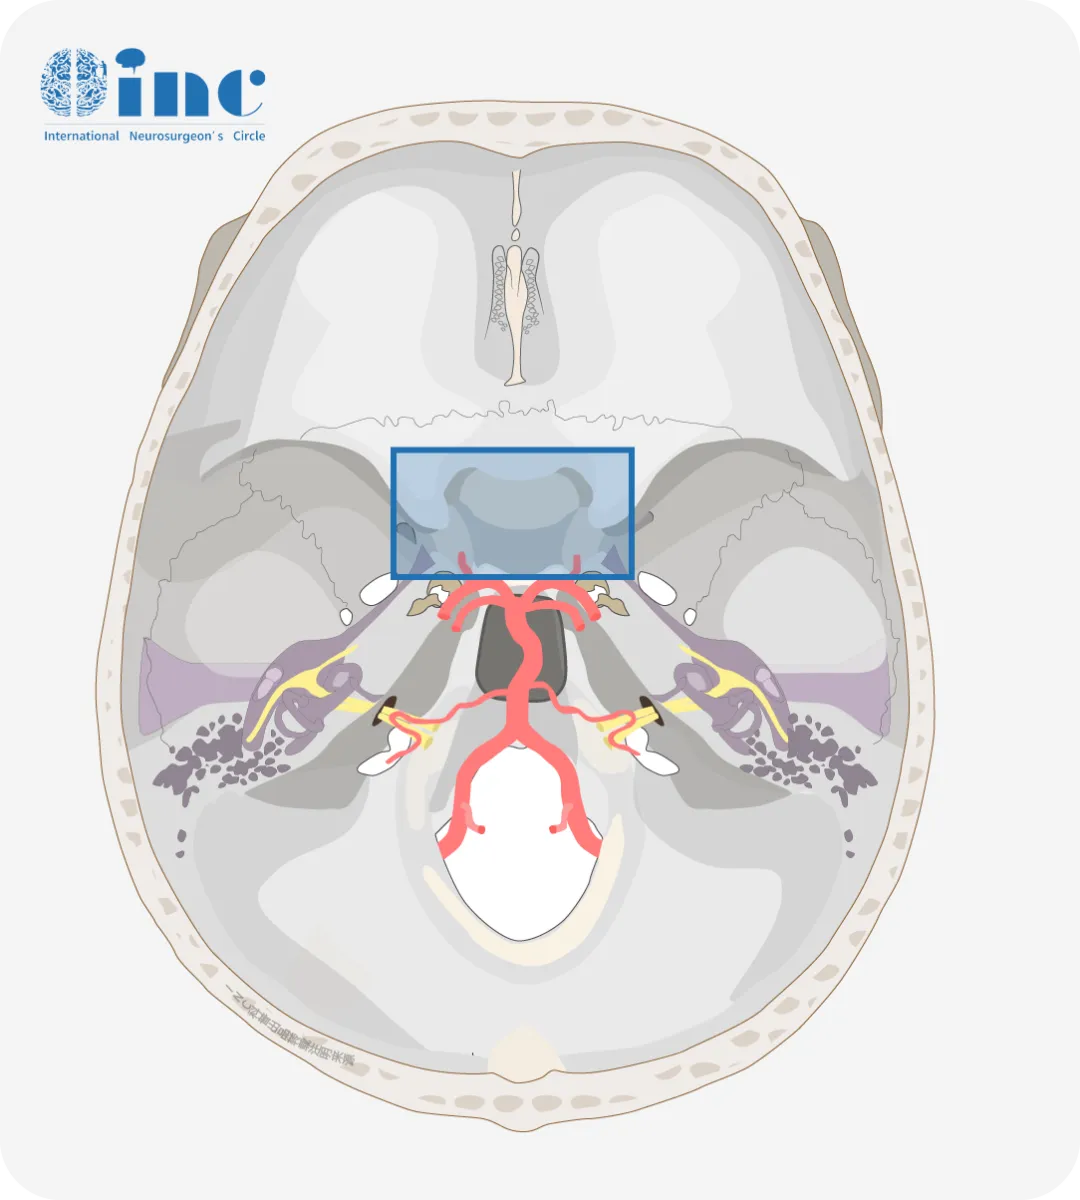

鞍區(qū)

圖示藍(lán)色框內(nèi)即為鞍區(qū)

鞍區(qū),蝶鞍區(qū)是指顱中窩中央部的蝶鞍及其周圍的區(qū)域,前界為前床突外側(cè)緣和前交叉勾的前緣,后界為后床突和鞍背,兩側(cè)為頸動脈溝,面積約為5.5c㎡。

鞍區(qū)的主要結(jié)構(gòu)有蝶鞍、蝶竇、垂體、視神經(jīng)、視交叉、下丘腦、海綿竇,頸內(nèi)動脈、大腦前動脈等重要結(jié)構(gòu),解剖范圍僅約3CM、結(jié)構(gòu)多、毗鄰關(guān)系復(fù)雜,是疾病的多發(fā)部位。

鞍區(qū)最常見的病變?yōu)槟[瘤樣的病變,在鞍旁多為腦膜瘤、鞍后多為脊索瘤,鞍上多為顱咽管瘤,鞍下多為蝶鞍腫瘤,鞍內(nèi)以垂體瘤多見。

鞍區(qū)是眾多關(guān)乎生命結(jié)構(gòu)的匯集地,如Willis環(huán)、海綿竇、垂體、下丘腦、多組顱神經(jīng)等......

鞍區(qū)腫瘤由于病變位置深在、毗鄰結(jié)構(gòu)復(fù)雜,歷來是神經(jīng)外科治療的難點。鞍區(qū)常見腫瘤包括:垂體腺瘤、顱咽管瘤、腦膜瘤、脊索瘤、拉克氏囊腫等。